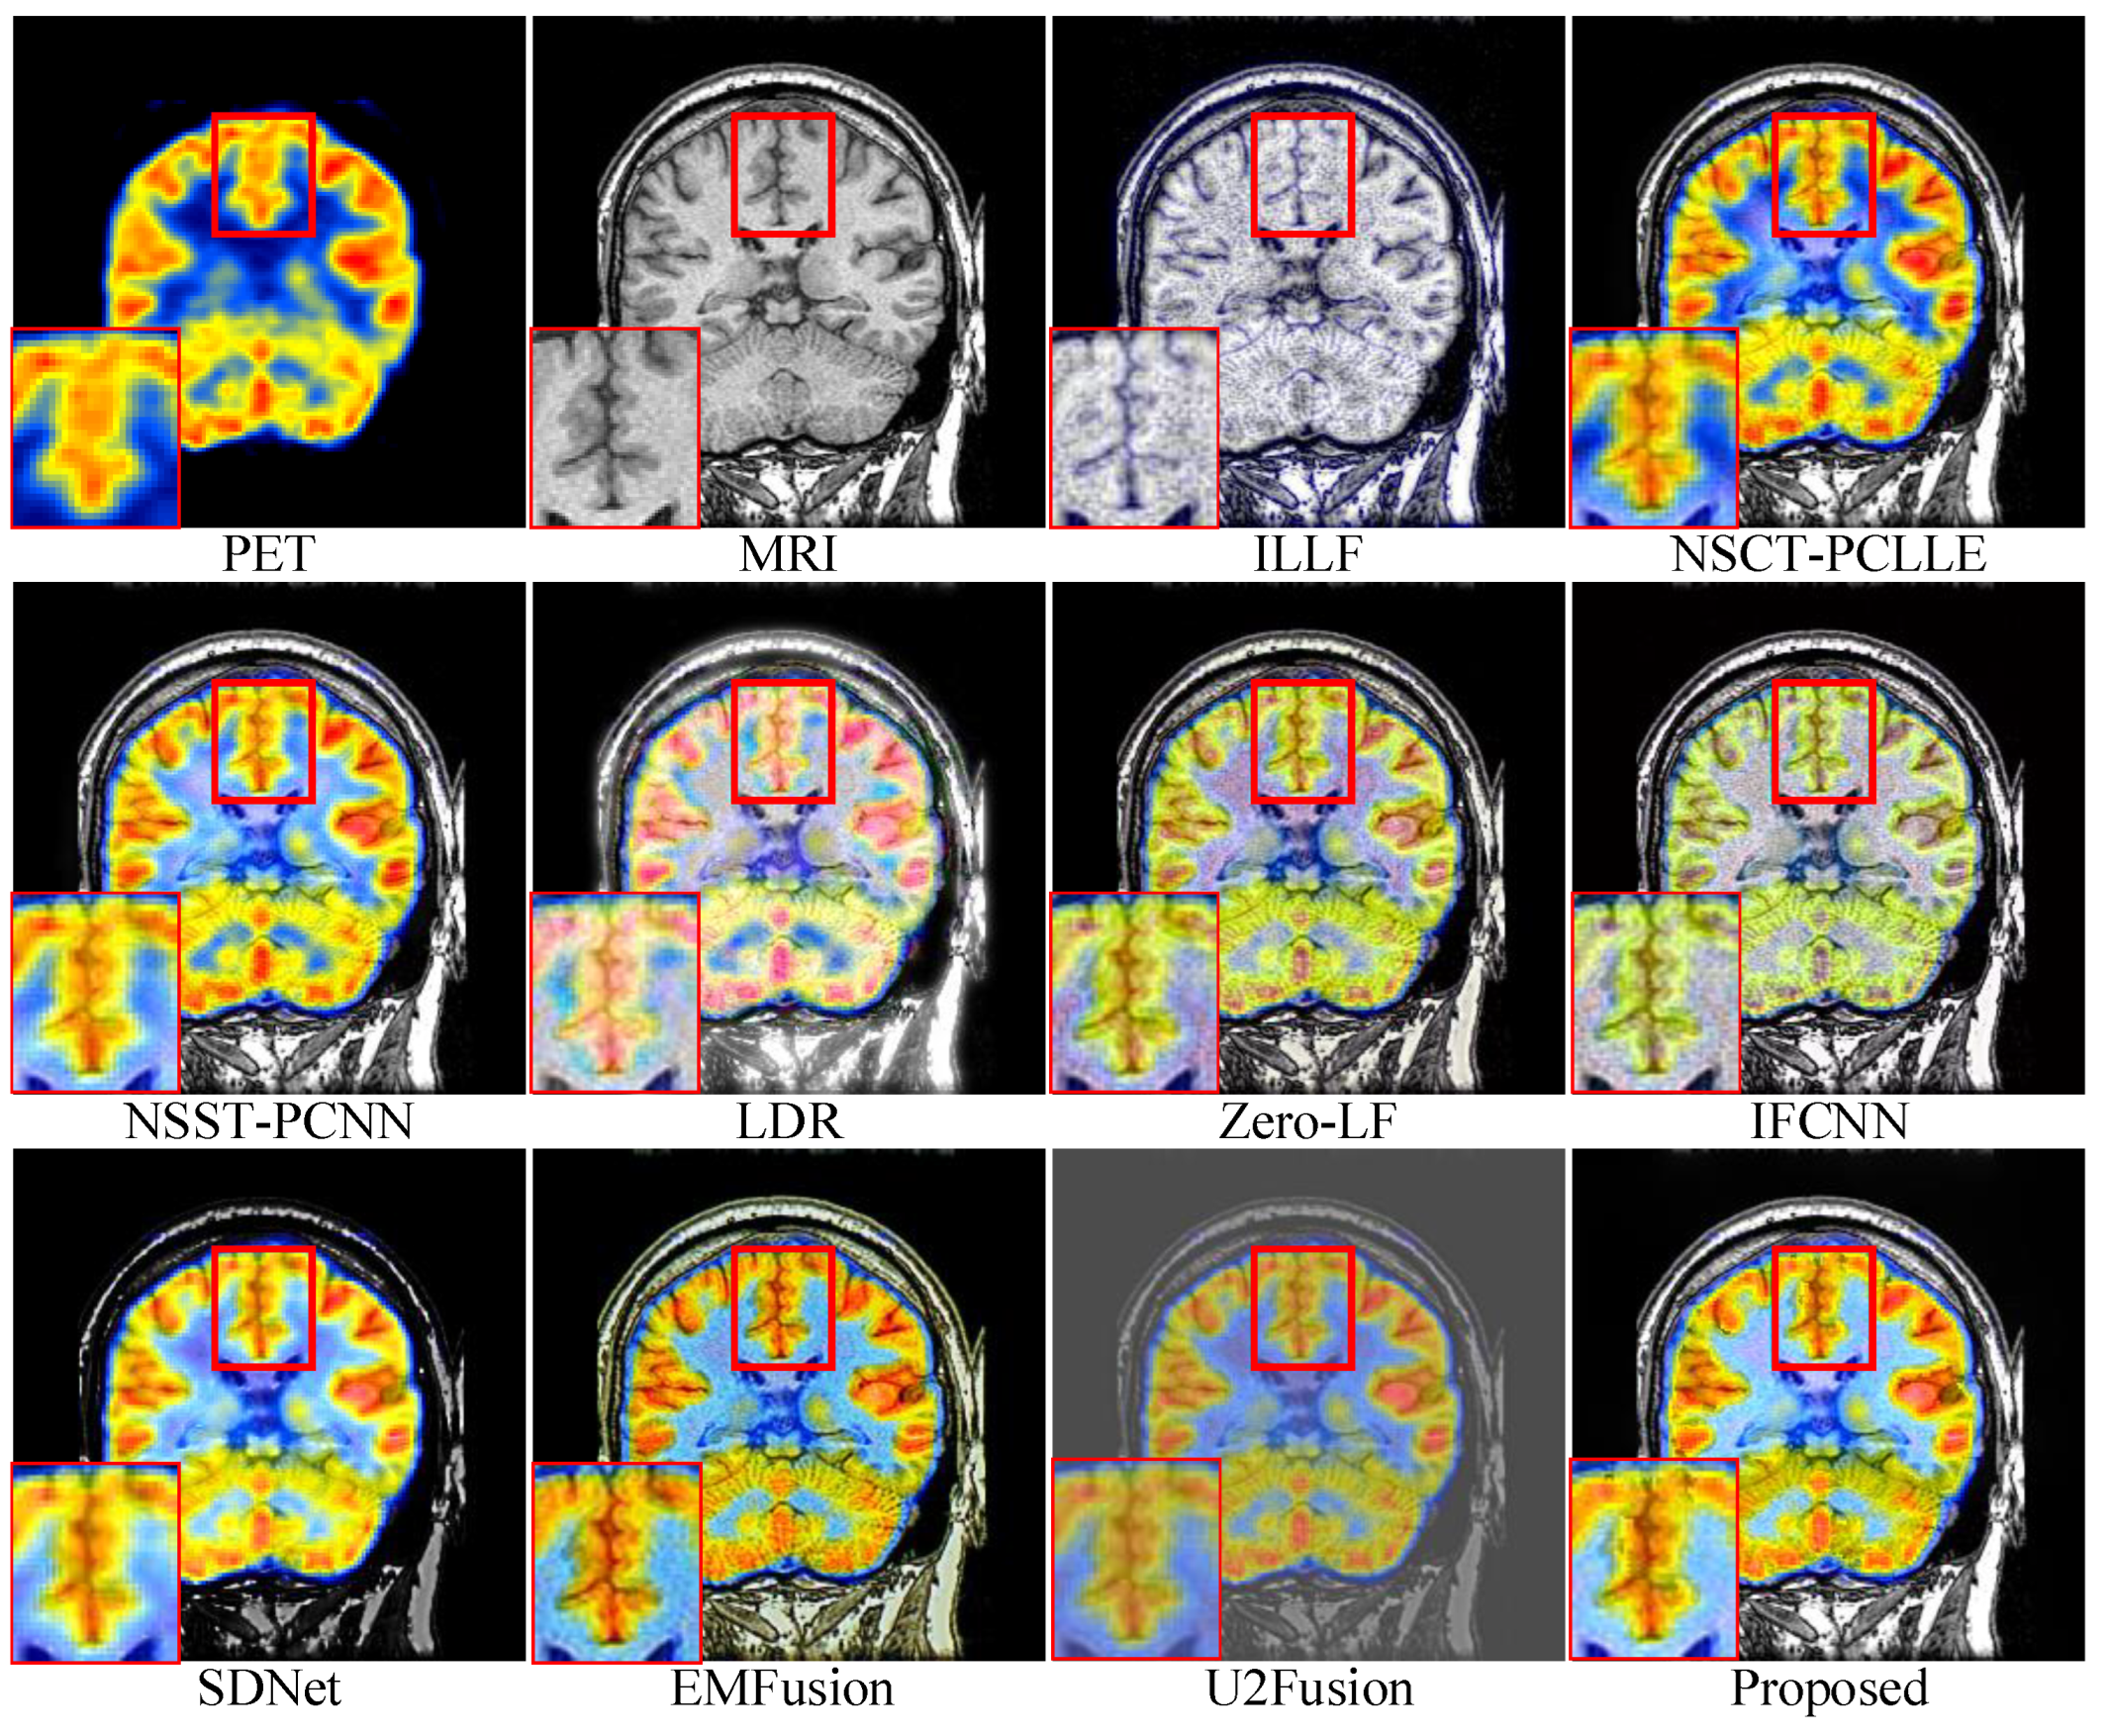

For conciseness, we have only shown the results of three sets of images in the subjective evaluation. Figure 5, Figure 6 and Figure 7 show the fusion results of different types of medical images obtained by different image fusion algorithms.

Figure 6.

Comparison of performances of various methods on the positron emission tomography (PET)-MRI source images. For a clear comparison, we select a same region (i.e., the red box) in each image and zoom in it in the bottom left corner.

Figure 6 shows a set of PET-MRI images fused by different methods. The fusion results of ILLF, LDR, Zero-LF, IFCNN, and U2Fusion show their insufficient ability in retaining the color in the PET images, which led to color distortion in the fusion results. LDR, SDNet, EMFusin, and U2Fusion performed poorly in retaining the luminance information of the MIR images; the luminance-oversaturation phenomenon occurred in the fusion results under LDR. Under SDNet, EMFusion, and U2Fusion, most of the energy from the MRI images was lost, particularly under SDNet, which led to a low overall illuminance in the images. The enlarged portion in the lower left corners shows that our method was able to retain the detailed part of the MIR image. Additionally, under our method, jagged edges can be observed in the fused image, while these edges were slightly missing under the other methods, demonstrating the superior performance of our method. Overall, Figure 6 indicates that our method could retain the structural information of the source image and outperformed the other methods in expressing intensity-based features.